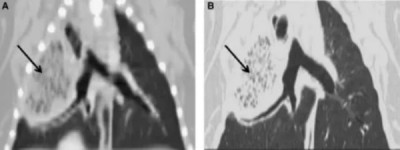

图3. 一只8岁杰克罗素梗犬在静脉注射造影剂后,因右中叶扭转的胸部横断计算机断层扫描(CT)图像。该肺叶增大并包含滞留气体(箭头)。心脏轮廓向左移位。右前叶向背侧移位并受压。

图 4. (A) 和 (B): 一只2岁巴哥犬右前叶扭转的胸部背侧重建计算机断层扫描(CT)图像。显示了使用细节算法的螺旋3 mm层厚图像(A)和使用骨算法及边缘增强的高分辨率横断1 mm层厚图像(B)。肺叶增大并包含滞留气体。通向右后叶的支气管移位并围绕增大的前叶弯曲(箭头)。右中叶塌陷并向内侧移位,在此图像上不可见。

图 5. 一只患右中叶扭转的比格犬的横断高分辨率计算机断层扫描(CT)图像。肺叶尖端指向背外侧方向(箭头),表明肺叶移位和旋转。气胸和轻度胸腔积液也可见。